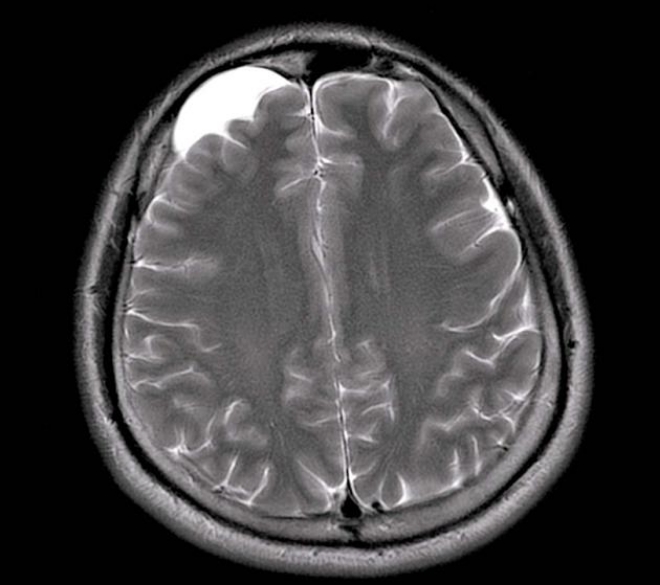

- Субэпендимальная. Причиной возникновения является плохое кровообращение. Отличается быстрым прогрессированием, что требует своевременной диагностики и адекватной терапии. Чаще всего страдает орган зрения.

Вне зависимости от того, какой метод будет выбран для лечения кисты головы, главное, своевременное ее обнаружение. Если во время не обратиться к специалистам, возможен такой страшнейший вид осложнения как гидроцефалия, часто приводящая к смерти больного.